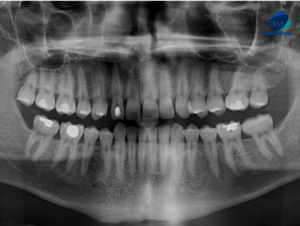

Paciente femenina acude a la sede de IDM- Miraflores para una tomografía computarizada para la evaluación de terceras molares. A la evaluación de la radiografía